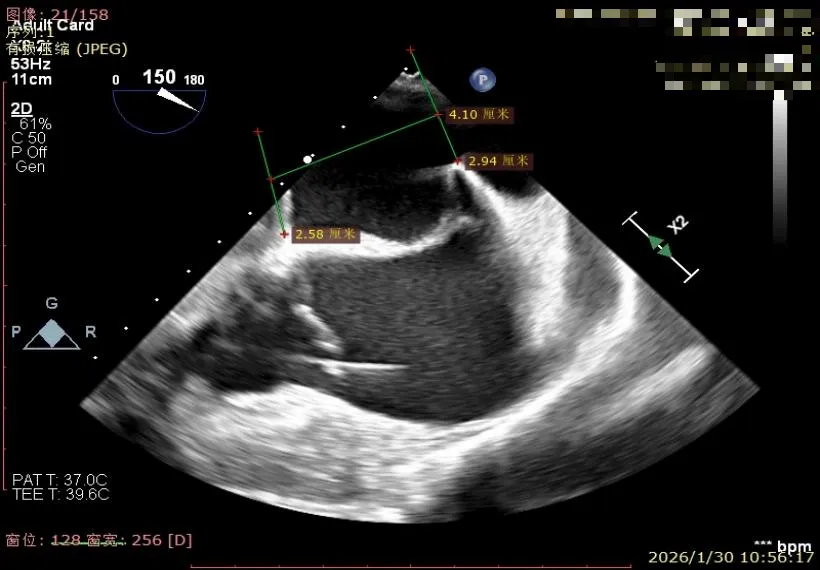

经胸超声报告提示:患者二尖瓣2区及3区前叶关闭时脱入左房,二尖瓣重度反流(MR 4+),患者LA前后径约52mm,LVEDD约68mm,LVESD约42mm,EF值:65%,经胸超声测二尖瓣瓣口面积约6.1cm2,主动脉瓣无冠瓣脱垂并中重度反流,三尖瓣中度反流,估测中度肺动脉高压。

经食道超声精细化测量:肺静脉逆流,房间隔可穿刺高度约4.2cm,Flail宽度约21mm,Flail高度约8mm,Flail Gap约4mm, 3区AML长约23mm、PML长约12mm、2区AML约32.2mm,PML约16mm。

房间隔可穿刺高度约4.2cm

Flail宽度约21mm,Flail高度约8mm

经胸短轴测得瓣口面积约6.1cm2

3区前叶长度约22mm,后叶长度约11.6mm

2区前叶长度约32.2mm,后叶长度约16mm

2区Flail Gap约4mm